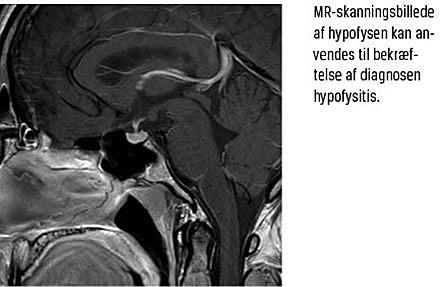

Diagnosen hypofysitis stilles biokemisk ved måling af samtlige hypofysehormoner (Tabel 2). Billeddiagnostisk foranstaltes en MR-skanning af hypofysen. Denne kan støtte diagnosen, men fund af normale

forhold ved en skanning udelukker ikke hypofysitis.